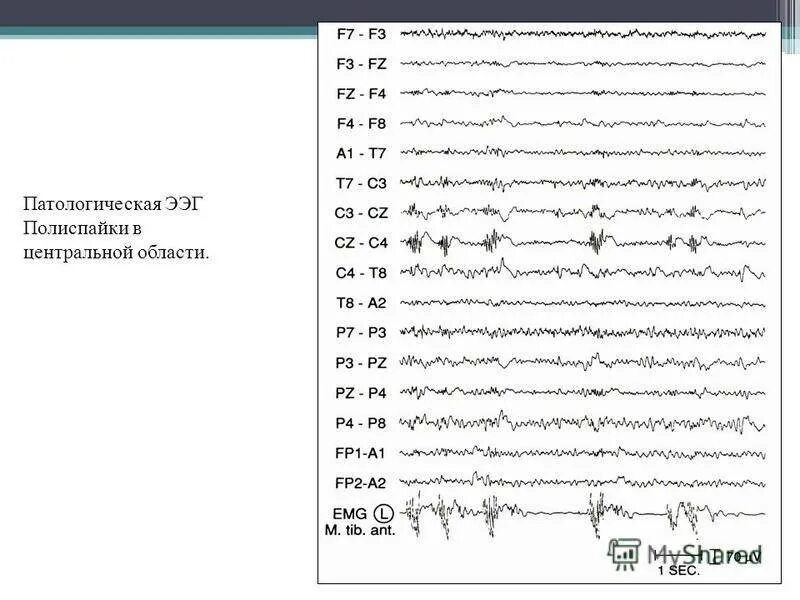

Для чего делают ээг